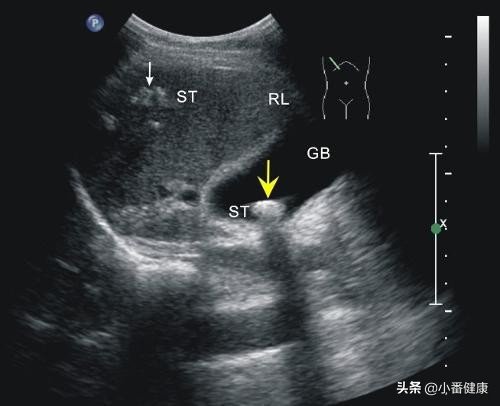

临床比较常见的转氨酶高诱因包括药物性、酒精、过度劳累、睡眠不足等,而这些都属于非肝炎诱因。当然,还包括一些疾病引起的转氨酶高,例如胆石症、脂肪肝、胆囊炎;还有一些比如肾病、心血管病等也是可以引起转氨酶升高的。

每一位乙肝大三阳,他们所处的免疫状态也不同,是可以通过指标复查判断的。例如,转氨酶因乙肝升高超出上限两倍者,进行抗病毒治疗才会收到效果。而对于胆石症、胆囊炎引起的转氨酶升高,只要治疗原发病后,随着病情稳定转氨酶也会恢复到正常水平。